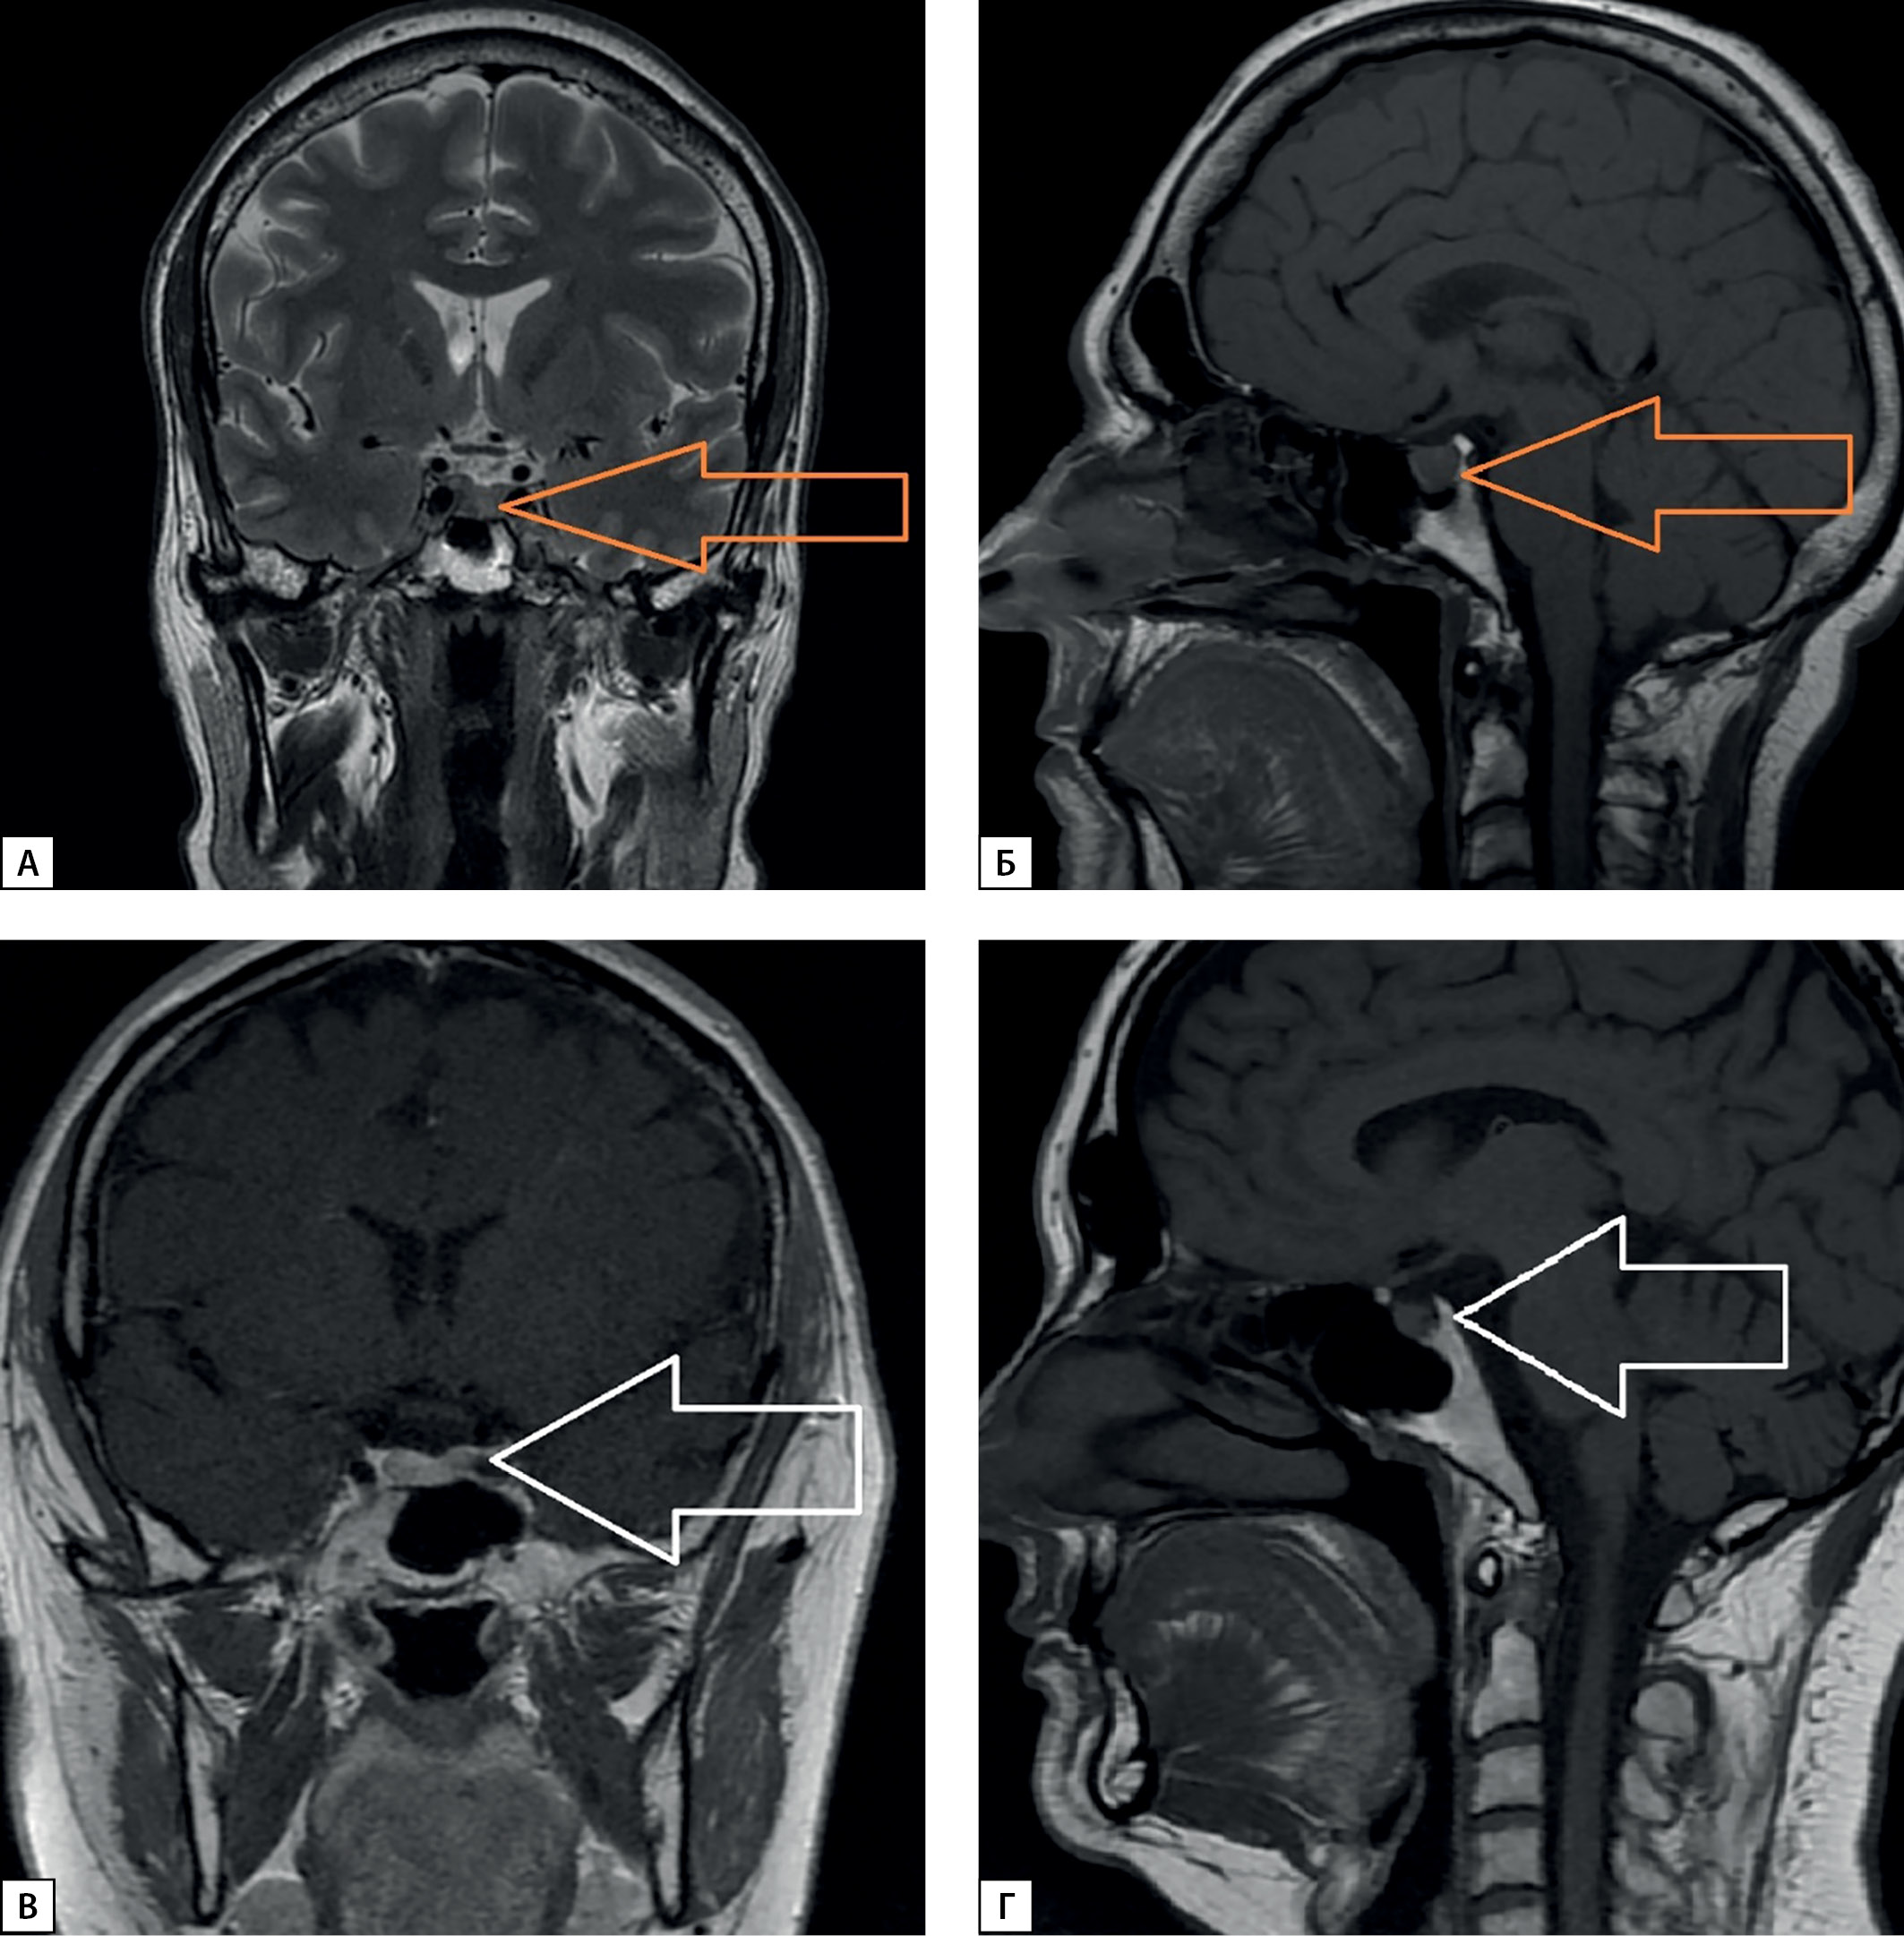

Пациентка Д. воздержалась от оперативного лечения в объеме «трансназальной аденомэктомии» из-за страха хирургического вмешательства и наличия сопутствующей сердечно-сосудистой патологии в виде акромегалической кардиомиопатии, артериальной гипертензии с эпизодическим повышением артериального давления до 180/90 мм рт.ст. на фоне медикаментозной терапии и атеросклероза аорты вследствие дислипидемии. С сентября 2019 г. инициирована медикаментозная терапия российскими аналогами соматостатина пролонгированного действия: Октреотид-депо 20 мг в/м 1 раз в 28 дней. Через неделю после начала терапии пациентка отметила улучшение общего самочувствия, уменьшение выраженности отечного синдрома, потливости, болей в суставах, через месяц при контроле лабораторных показателей достигнута медикаментозная ремиссия, сохраняющаяся по настоящее время: уровень ИФР-1 в крови в пределах 174,9–193,7 нг/мл (17–238 нг/мл). По результатам МРТ головного мозга от 2021 г. отмечалась положительная динамика в виде уменьшения размеров аденомы: в марте — 6,5х6,0х8,0 мм, объем аденомы — 156 мм3, в декабре — 6,0х7,1х7,0 мм, объем 149,1 мм3 (рис. 2В, 2Г).

Рисунок 2. МРТ головного мозга с контрастным усилением:

А, Б — макроаденома гипофиза до начала лечения; В, Г — микроаденома гипофиза спустя 3 года медикаментозного лечения АСС.

Figure 2. Сontrast enhanced magnetic resonance imaging of the brain.

A, B — (pituitary macroadenoma before treatment); C, D — Pituitary microadenoma after 3 years of ACS treatment.